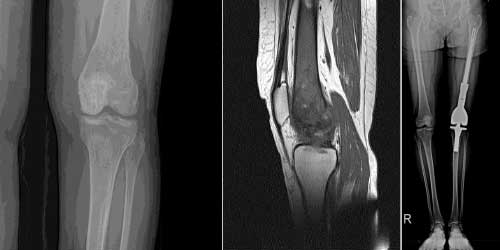

Her ameliyatın olduğu gibi kemik ve yumuşak doku tümör ameliyatlarının da riskleri vardır. Bu riskleri genel ve yapılan ameliyata özgü olmak üzere kabaca iki başlık halinde gruplandırabiliriz. Öncelikle anestezi ile ilgili risklerin anestezi uzmanı tarafından (...)

Ameliyat sonrası takip ve kontrol hastanın ameliyat masasında uyanması ile başlar. Özellikle damar ve veya siniri ilgilendiren ameliyatlarda hasta ameliyat masasından alınmadan ekstremitenin dolaşımı ve ilgili sinirin fonksiyonu kontrol edilir.